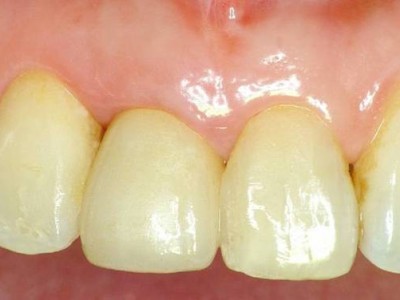

환자의 치아 모양·색상에 맞춰 맞춤 제작된 크라운을 부착해 자연스러운 심미성과 기능을 회복합니다.

A+ 임플란트의 다양한 케이스를 확인해보세요.